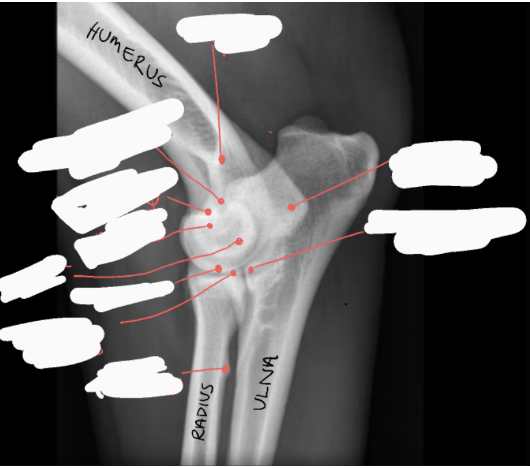

Label the image

A